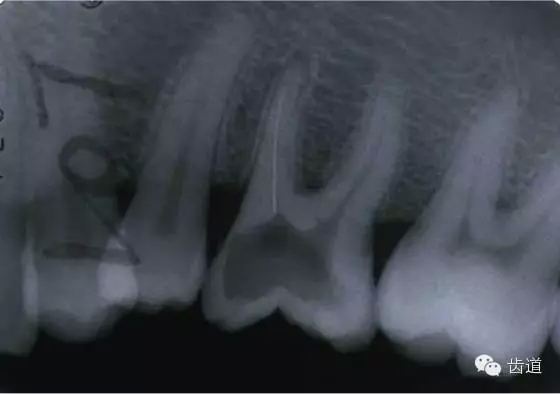

左下7根充后下唇麻木

左下5根管預(yù)備后下唇麻木